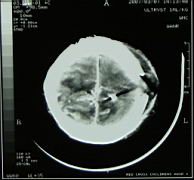

Gunshot fragments in the brain of a 4 year old boy, victim of stray bullets in a township gun battle |